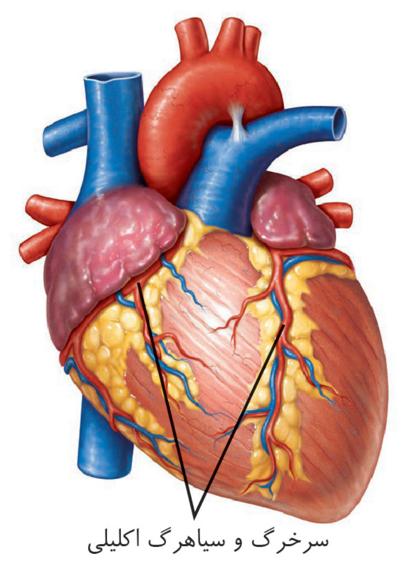

به هر کلیه، یک سرخرگ وارد میشود. انشعابات این سرخرگ از فواصل بین هرمها عبور میکند و در بخش قشری به سرخرگهای کوچکتری تقسیم میشود. انشعاب انتهایی این سرخرگها، سرخرگ آوران نامیده میشود. سرخرگ آوران در کپسول بومن، شبکه مویرگی کلافک را میسازد. خون از طریق سرخرگ آوران به کلافک وارد میشود و از طریق سرخرگ وابران آن را ترک میکند.

سرخرگ وابران در اطراف لولههای پیچخورده و قوس هنله، شبکه مویرگی دورِ لولهای را میسازد. این مویرگها به یکدیگر میپیوندند و سیاهرگهای کوچکی بهوجود میآورند که پس از عبور از فواصل بین هرمها سرانجام سیاهرگ کلیه را میسازند. این سیاهرگ، خون را از کلیه بیرون میبرد.